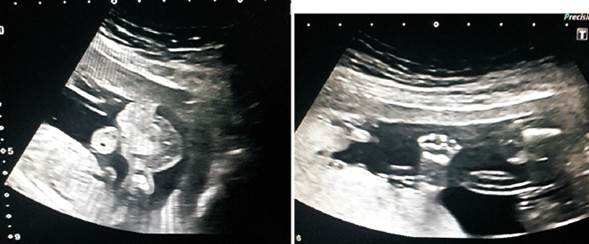

La paciente es derivada a nuestro centro, la Unidad de Medicina fetal (UMP) del Centro Hospitalario Pereira Rossell, para revalorar. Cursando un embarazo de 15 ± 6 semanas, realizamos diagnóstico de embarazo monocorial monoamniótico, identificándose un feto vivo y sano, con crecimiento acorde para la edad gestacional (figura 1) y conjuntamente una masa amorfa sin actividad cardíaca (figura 2), con edema subcutáneo generalizado de 35 x 20 x 28 mm (dimensiones aumentadas con respecto a un estudio previo) por lo que se plantea diagnóstico de embarazo gemelar con feto hidrópico en un caso de secuencia TRAP.

Figura 2: En la imagen izquierda se visualiza masa amorfa con edema generalizado a su alrededor. En imagen derecha, parte de la masa amorfa donde se identifica un miembro inferior. No se identifica cráneo ni miembros superiores.